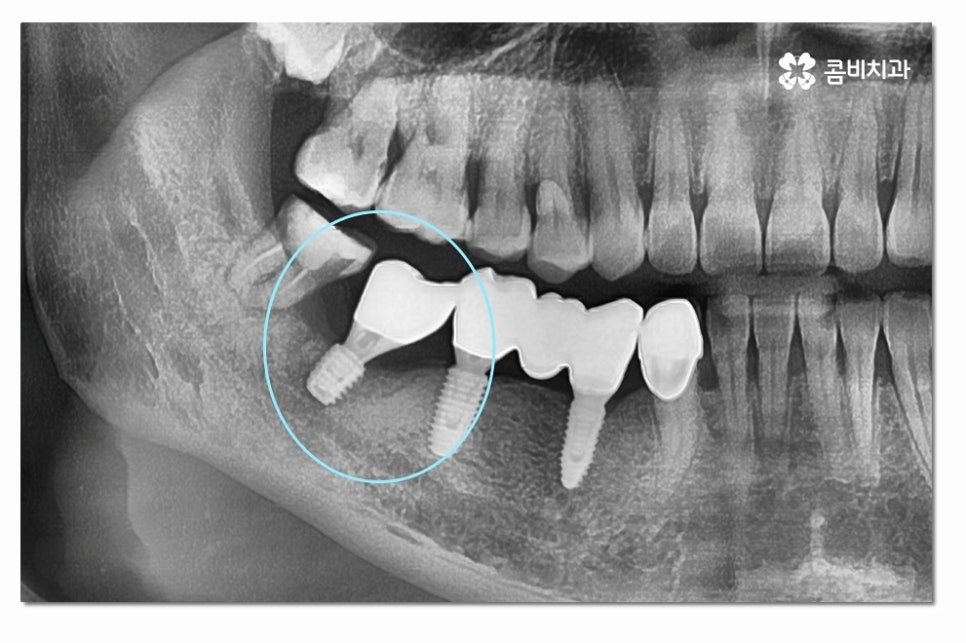

어금니를 잃게 된 상태에서 그대로 방치하게 되면 저작력이

저하되고 반대쪽 치아로만 식사를 하다 보면

소화불량이나 턱관절 장애를 겪을 수 있어요.

또한 치열이 망가질 우려도 있고 시간이 지날수록

잇몸이 점점 흡수되기 때문에 추후에는 어금니임플란트

치료를 하더라도 잇몸 뼈가 부족해서 치료가 어려워지거나

뼈이식을 추가로 받아야 하는 경우도 있어요.